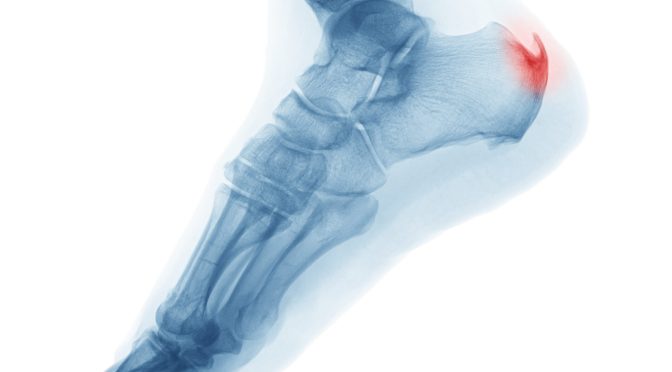

Stress Fractures

Repeated impact due to activities like running or jumping can lead to stress fractures, which are tiny cracks in the bones of the feet. Players who play frequently without proper rest are at a higher risk, as the constant pounding on the court can weaken the bones over time. Stress fractures often develop gradually, starting as mild pain that worsens with continued activity. Pickleball players who play frequently or for long periods, wear inadequate footwear or have poor body mechanics are more vulnerable to stress fractures.